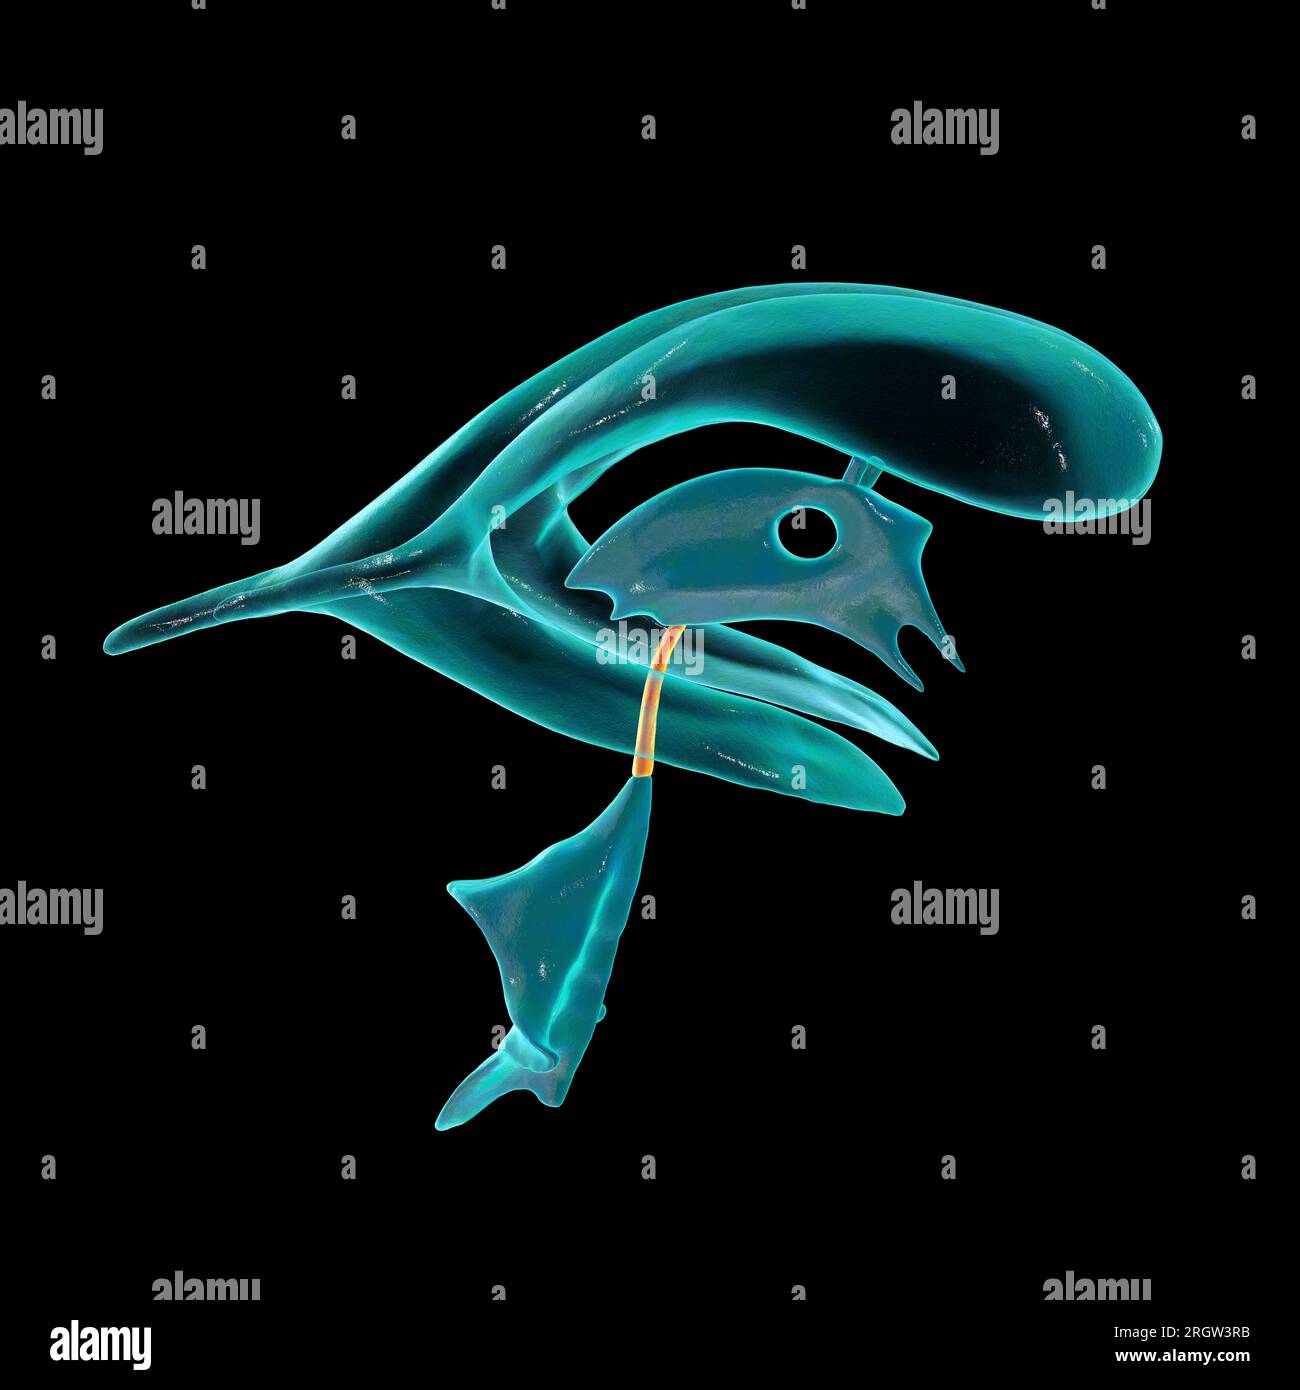

RF2T7NGWH–Ventrikel und zerebrales Aquädukt laterale Röntgenansicht 3D-Rendering-Illustration. Menschliches Gehirn und Ventrikelsystem Anatomie, Medizin, Gesundheitswesen, Scienc

RF2T7NGWK–Ventrikel und zerebraler Aquädukt lateral in Farben Röntgenbild-3D-Rendering-Illustration. Menschliches Gehirn und Ventrikelsystem Anatomie, medizinisch, gesund

RF2T7NGWR–Ventrikel und Hirn-Aquädukt-Röntgenprofil Nahansicht 3D-Rendering-Illustration mit Körperkonturen. Anatomie des menschlichen Gehirns und des Ventrikelsystems,

RF2T7NGWW–Ventrikel und zerebraler Aquädukt in Farben Röntgenprofil Nahansicht 3D-Rendering-Illustration. Anatomie des menschlichen Gehirns und des Ventrikelsystems, medizinisch,

RF2T030FH–Röntgenprofilansicht des Sylvius oder des zentralen Aquädukts des Gehirns 3D-Rendering-Illustration. Menschliche Körperanatomie, Medizin, Biologie, Wissenschaft, Neurowissenschaft,

RF2T6AR8J–3D-Rendering-Illustration für die Röntgenansicht des Gehirns oder des Sylvius aquädukt. Anatomie des menschlichen Gehirns und des Ventrikelsystems, Medizin, Gesundheitswesen, Biologie, Wissenschaft,

RF2T6AR96–Röntgenprofil des Gehirns oder sylvius aquädukt Nahansicht 3D-Rendering-Illustration mit Körperkonturen. Anatomie des menschlichen Gehirns und des Ventrikelsystems, med